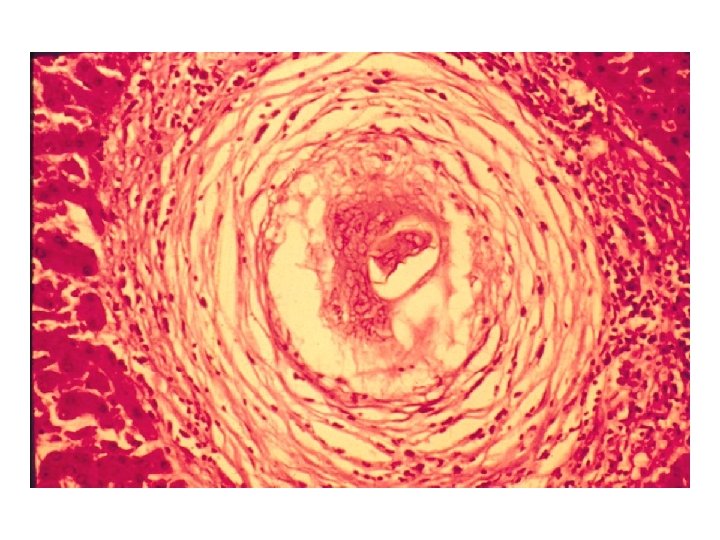

IMUNIDADE A BACTÉRIAS INTRACELULARES Imunidade resultando em cura Mycobacterium tuberculosis Rx de tórax mostrando calcificação no hilo pulmonar esquerdo após cura da tuberculose primária Alteração da resposta imune resultando em lesão Mycobacterium leprae pólo tuberculóide pólo lepromatoso M. tuberculosis Granuloma pulmonar